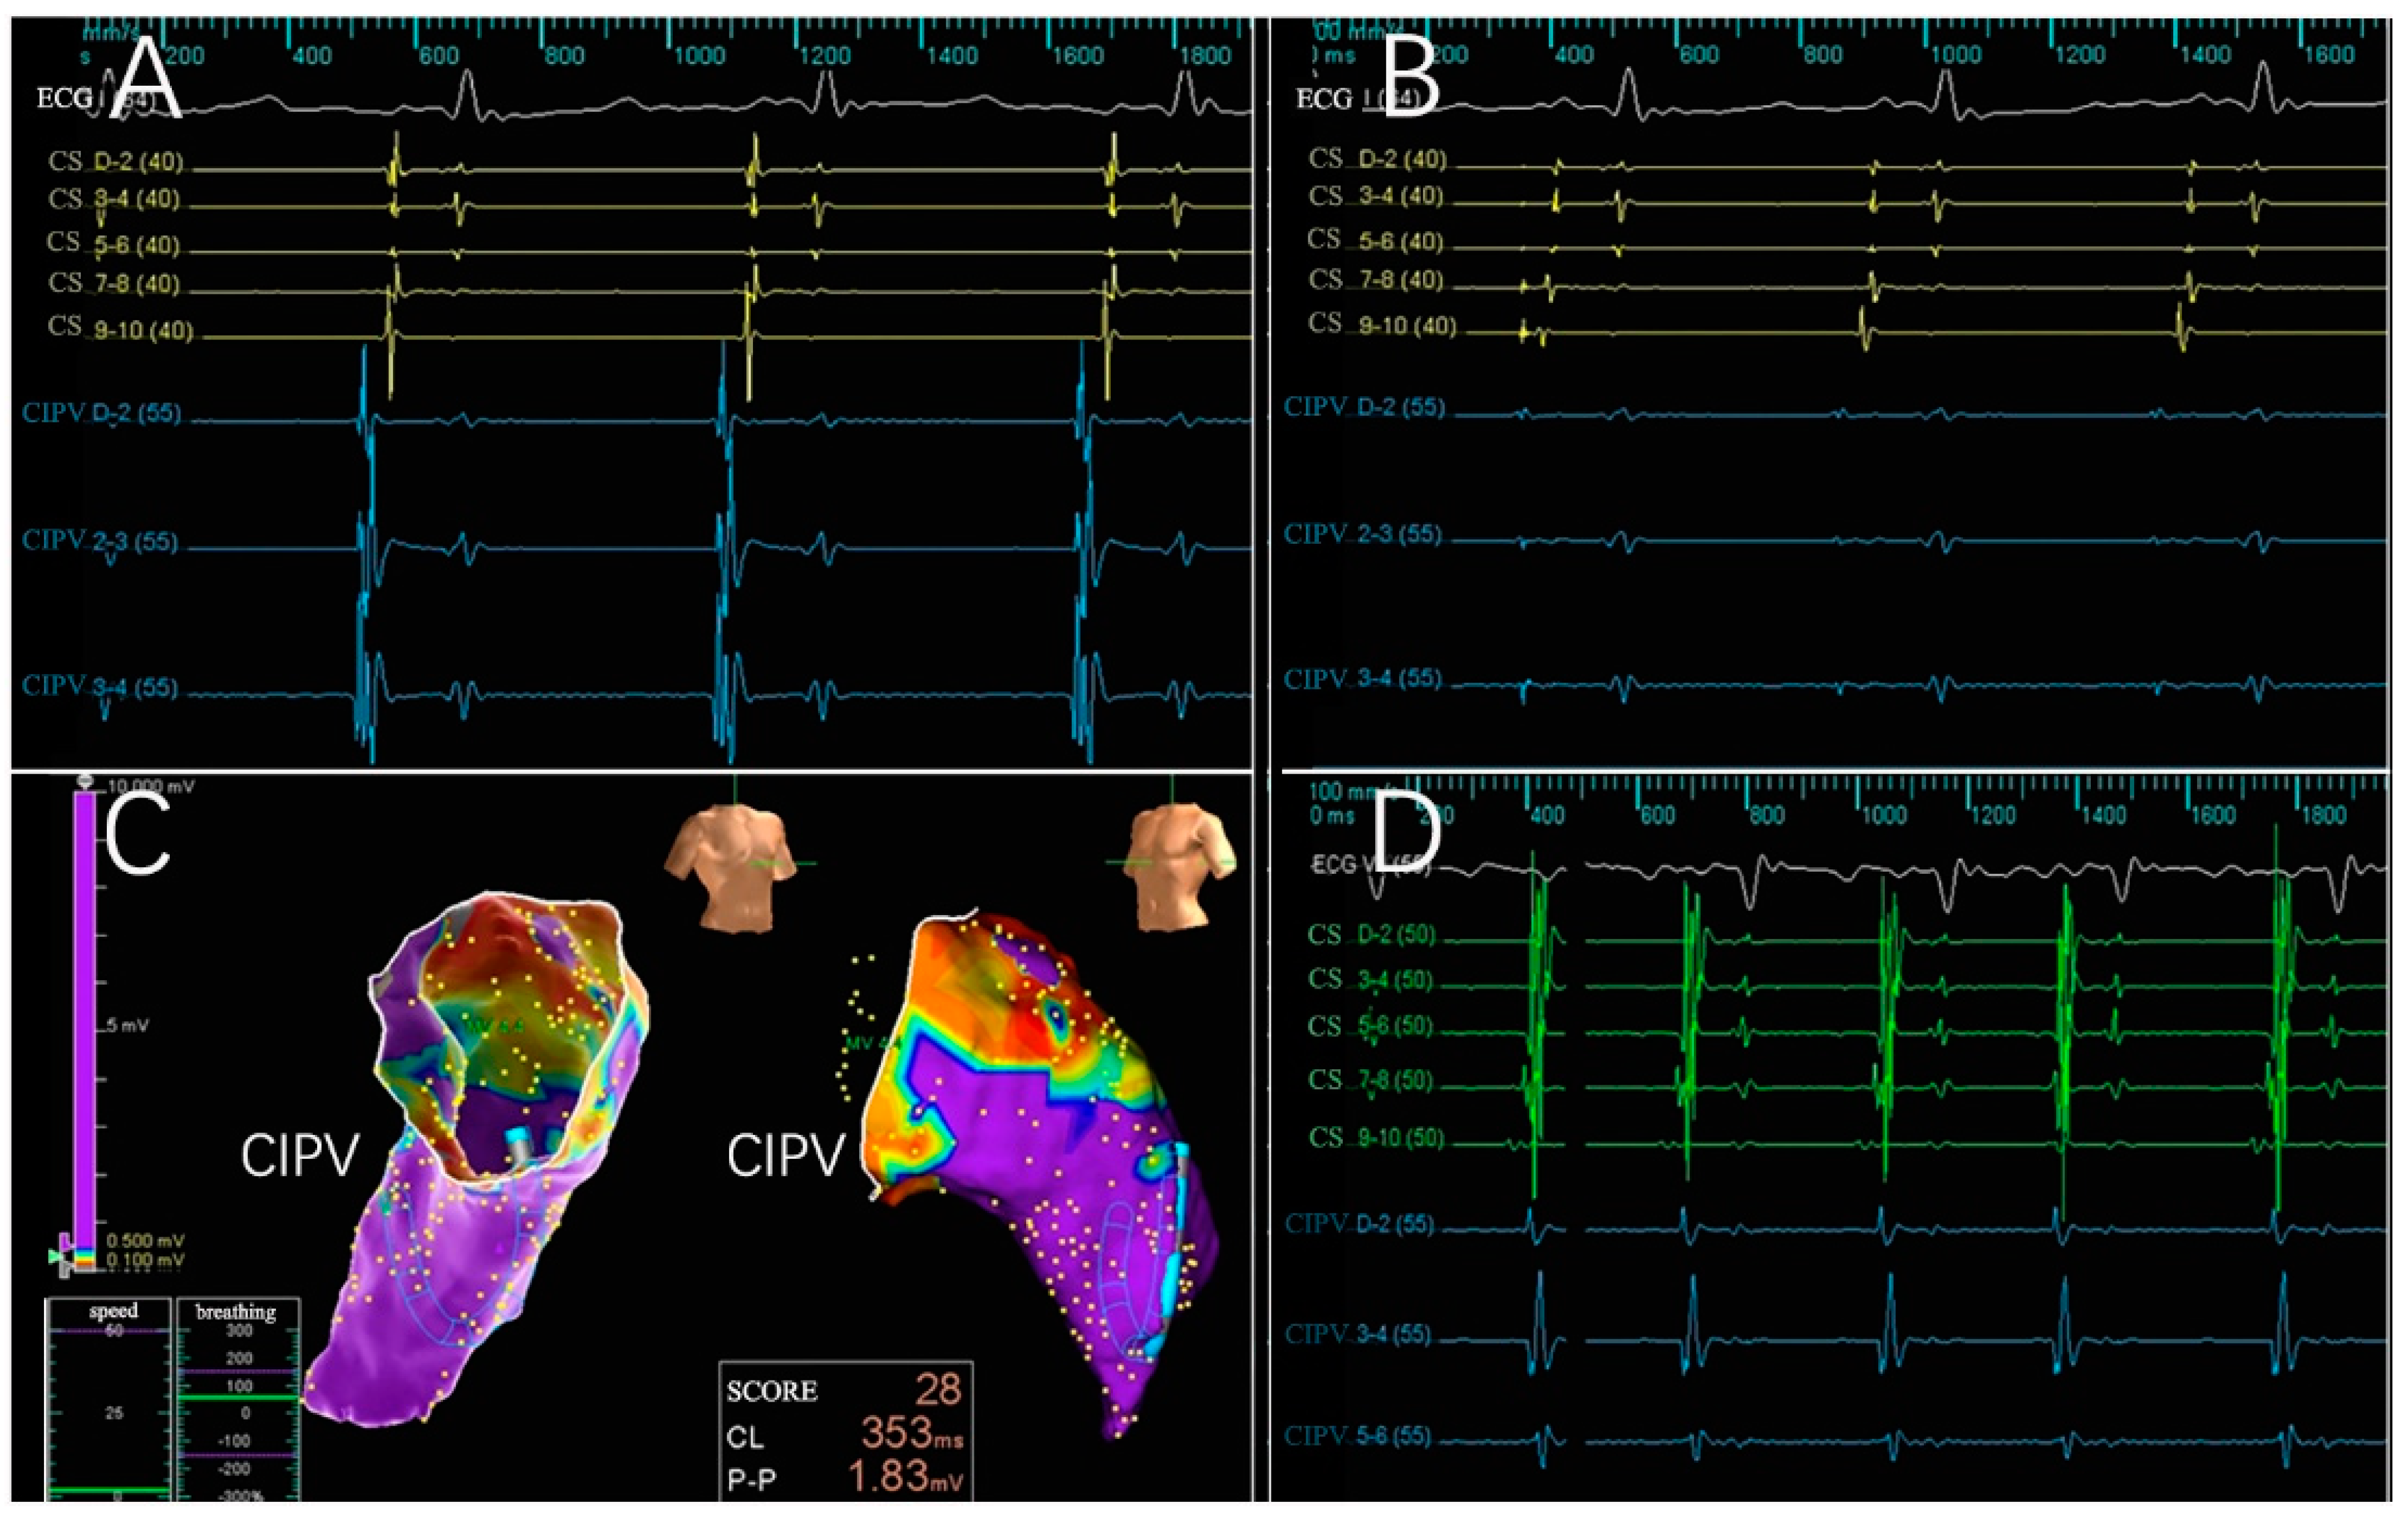

3.2. Electrogram, Voltage Mapping, and Complications